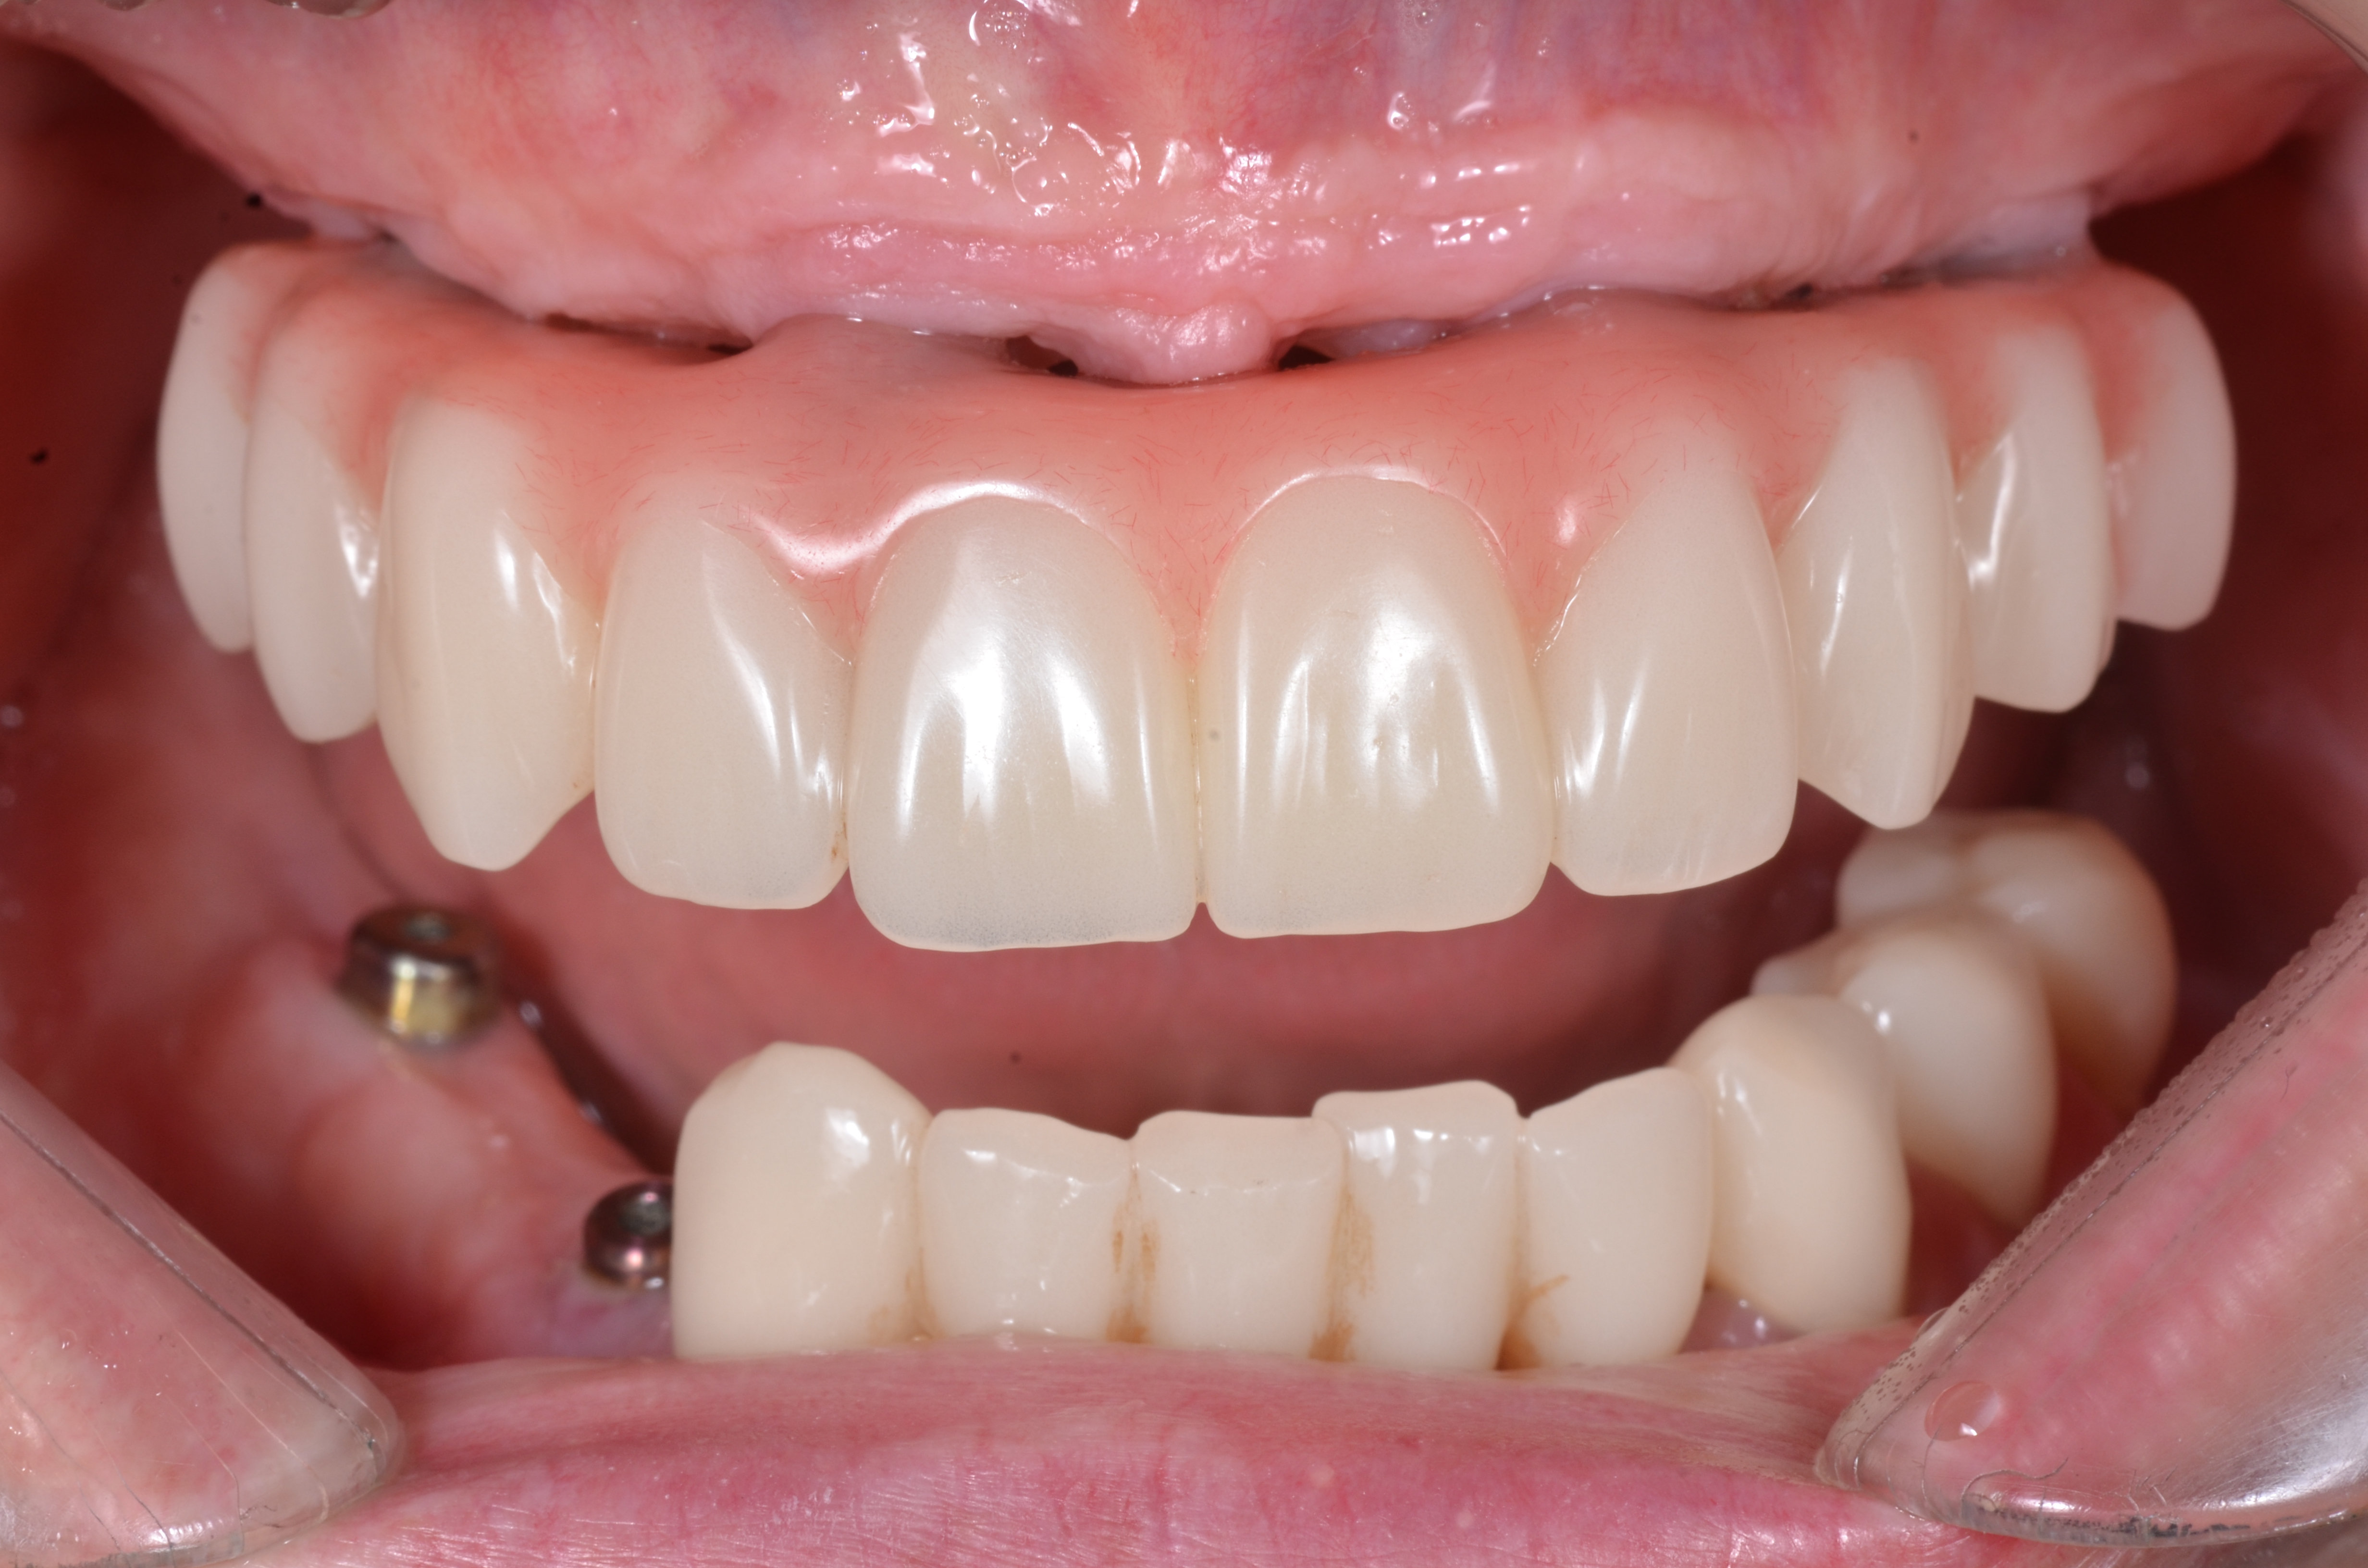

С эстетической и функциональной точки зрения провели диагностические оценочные манипуляции, согласовали с пациентом форму и цвет будущих зубов постоянной конструкции. Был изготовлен титановый фрезерованный каркас с индивидуальными абатментами NobelProcera® (рис. 44), с последующим изготовлением коронок из Диоксид циркония и имитацией розовой десны (рис. 45).

Через 8 месяцев после имплантации была зафиксирована несъёмная мостовидная керамическая конструкция с титановым каркасом по методике «All – on – 4» (рис. 46).

Благодаря междисциплинарному подходу при реабилитации стоматологических пациентов и богатому опыту нашей команды, нам удалось полноценно восстановить зубной ряд не только с эстетической точки зрения а, также восстановить его все функциональные параметры (рис. 47, 48,49).

На нижней челюсти с целью сохранения имеющихся функционально-полноценных зубов на возможный длительный срок провели их подготовку к протезированию и на этапе временного протезирования создали новые уровни биологической ширины вокруг каждого зуба, для защиты и восстановление утраченных зубов покрыли их несъёмным мостовидным протезом.